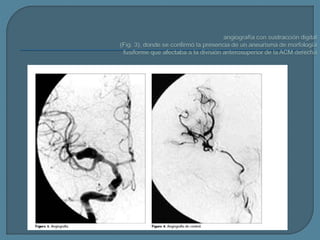

Este documento describe los aneurismas fusiformes, que afectan los vasos largos que no se ramifican y pueden ser agudos o crónicos. El principal signo diagnóstico es un segmento fusiforme largo o una dilatación arterial ovoidea. La tomografía computarizada y la resonancia magnética nuclear pueden usarse para identificar un vaso ectásico dilatado con señales de intensidad mixta. Los aneurismas fusiformes pueden ser ateroescleróticos o no ateroescleróticos.